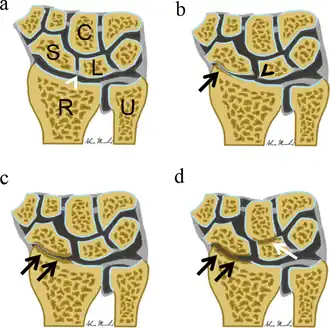

Scapholunate advanced collapse is a radiographic diagnosis. The Watson and Ballet classification identifies three stages of progressive wrist osteoarthritis that can be identified on a standard posterior-anterior (PA) wrist x-ray.

Stage I SLAC wrist

Stage I SLAC wrist involves the distal radioscaphoid joint.[3] The PA wrist x-ray will demonstrate radial styloid beaking (or localized scaphoid fossa arthrosis beginning at the radial styloid tip) and sclerosis and joint space narrowing of the radioscaphoid joint.[2]

Stage II SLAC wrist

Stage II SLAC wrist involves the entire radioscaphoid joint.[3] The PA wrist x-ray will demonstrate sclerosis and joint space narrowing between the entire radioscaphoid joint. [2]

Stage III SLAC wrist

Stage III SLAC wrist involves the entire radioscaphoid joint and the capitolunate joint.[3] The PA wrist x-ray will demonstrate sclerosis and joint space narrowing between the lunate and capitate. Over time, the capitate will migrate proximally into the space created by the scapholunate dissociation.[2] The radiographic findings in Stage III SLAC wrist are synonymous with the Terry-Thomas sign, indicating complete scapholunate dissociation.[2]